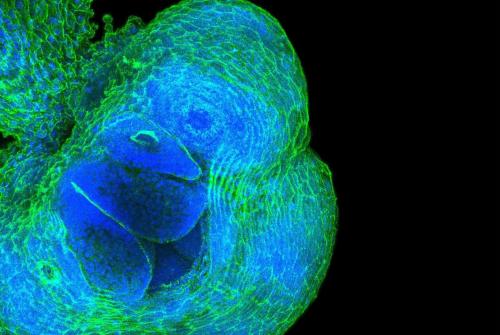

After hundreds of votes across social media platforms, the image crowned the winner was ‘A 3D snapshot of the hidden highways in childhood kidney cancer', entered by a team of multidisciplinary researchers at GOSH and UCL GOSH ICH.

This tangle of blues and purples peppered with gold, shows the lymph network (blue) within a kidney tumour alongside other structures such as blood vessels (purple) and immune cells (yellow). These ‘hidden highways’ are usually responsible for waste disposal, however cancers can hijack the system and use them to spread tumour cells around the body.

These systems are incredibly hard to see using traditional microscope techniques. Through collaboration, the team brought their unique skills together to generate this image using a new 3D imaging technique to view the lymph network within the tumour in high detail, to better understand how cancers grow and spread.

Overall winner and YPAG favourite: A 3D snapshot of the hidden highways in childhood kidney cancer

Pictured above are just some of the team that helped to create the winning image. The multidisciplinary team are looking at how cancers grow and spread through lymph networks. The hope is that this will help them understand whether the size of the network can predict how well children respond to chemotherapy, or if these highways influence the likelihood of cancer spread.